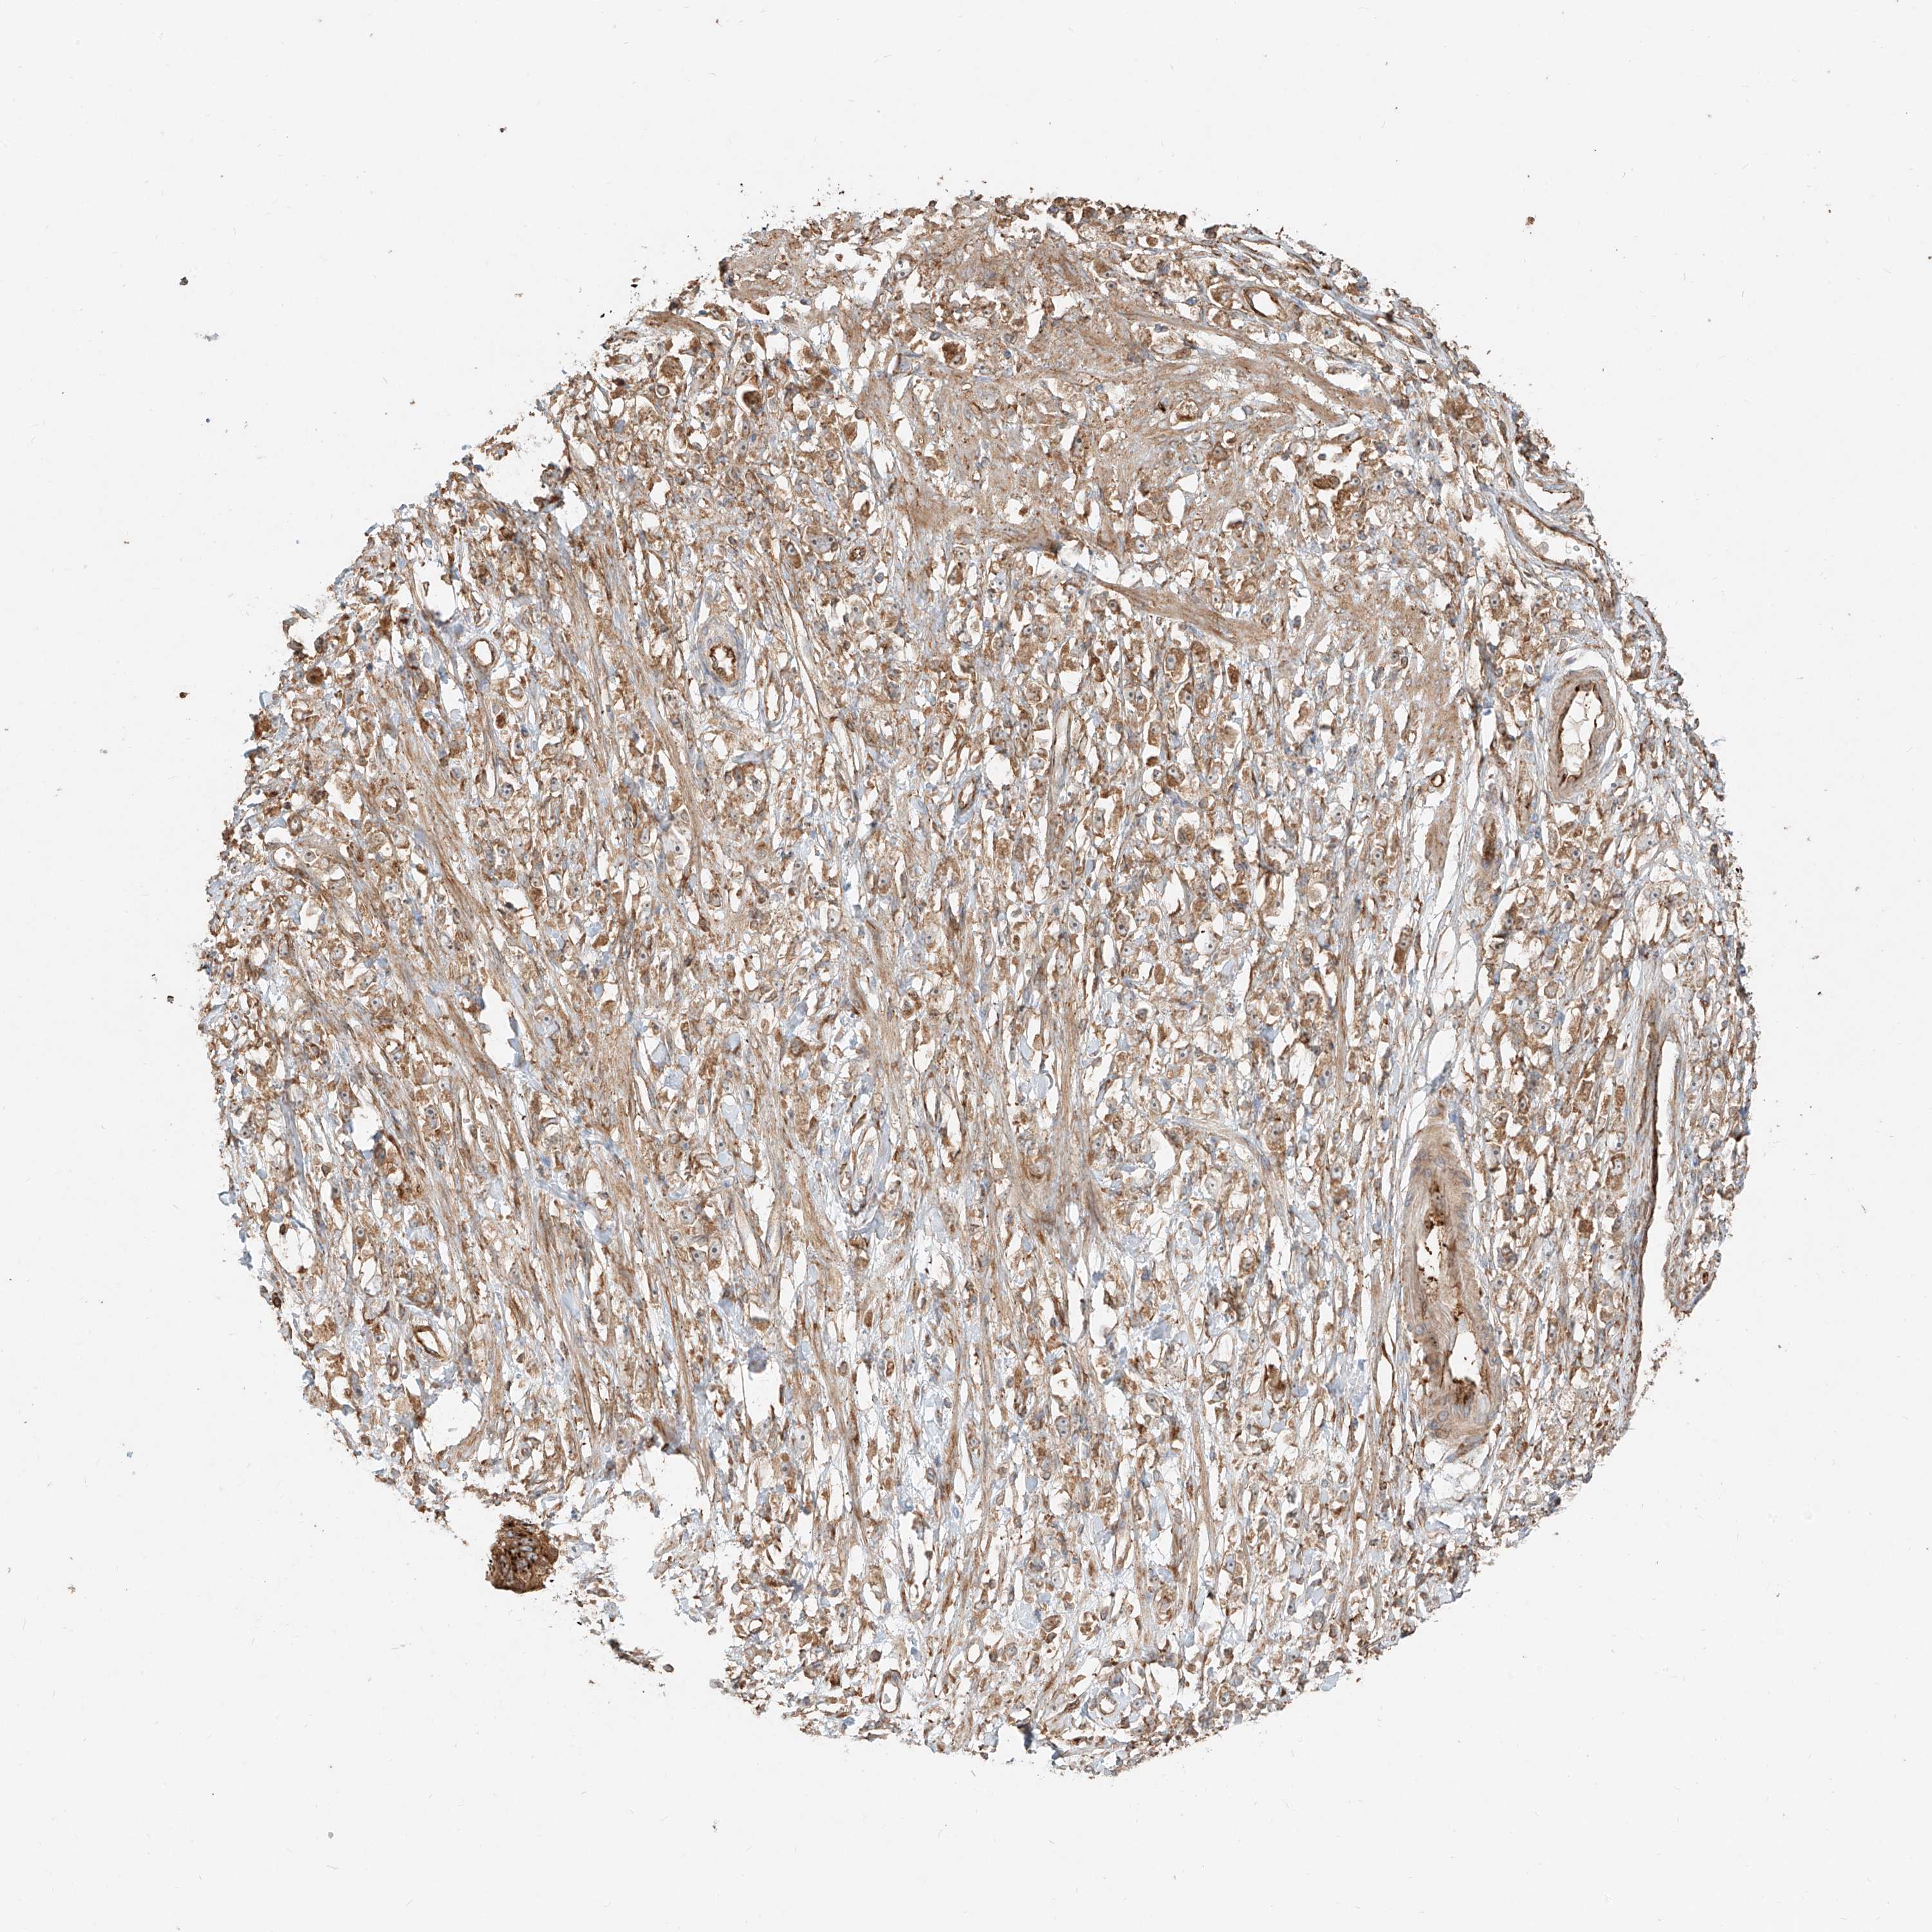

STOMACH CANCER - Protein expressioni

A mouse-over function shows sample information and annotation data. Click on an image to view it in a full screen mode. Samples can be filtered based on level of antibody staining by selecting one or several of the following categories: high, medium, low and not detected. The assay and annotation is described here.

Note that samples used for immunohistochemistry by the Human Protein Atlas do not correspond to samples in the TCGA dataset.

Antibody stainingi

Antibody staining in the annotated cell types in the current human tissue is reported as not detected, low, medium, or high, based on conventional immunohistochemistry profiling in selected tissues. This score is based on the combination of the staining intensity and fraction of stained cells.

Each image is clickable and will lead to virtual microscopy that enables deeper exploration of all samples and also displays staining intensity scores, fraction scores and subcellular localization as well as patient and tissue information for each sample.

Antibody HPA031410

Staining

High

Medium

Low

Not detected

Intensity

Strong

Moderate

Weak

Negative

Quantity

>75%

75%-25%

<25%

None

Location

Nuclear

Cytoplasmic/membranous

Cytoplasmic/membranous,nuclear

Adenocarcinoma, NOS